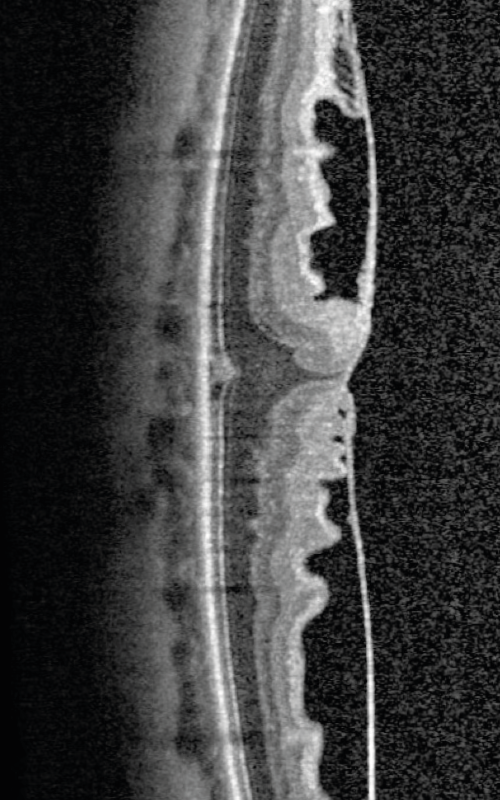

Cas Clinique – quand une CRSC se complique…

Ce cas illustre la complexité du spectre des pachychoroïdes et rappelle que toute CRSC atypique ou persistante doit faire rechercher une néovascularisation associée. L’imagerie multimodale est ici essentielle pour affiner le diagnostic et orienter la prise en charge.